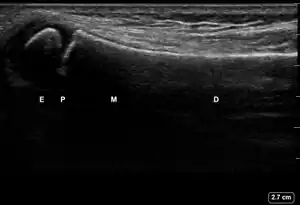

| 1 | Angulation of the distal bone segment[14] | ![]() Ultrasound view of angulation of distal bone segment (shown by arrow). E = epiphysis; P = physis; M = metaphysis; D = diaphysis. | |